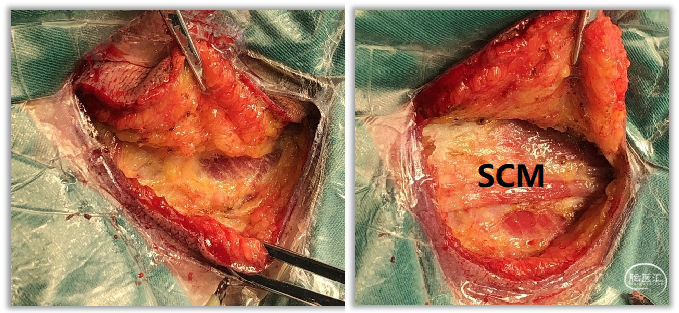

▼5.在帽状腱膜下层用电刀或剪刀分离,暴露胸锁乳突肌SCM。

为避免皮瓣过薄,必须在暴露肌肉层后方可继续剥离皮瓣,将脂肪层均留给皮瓣。